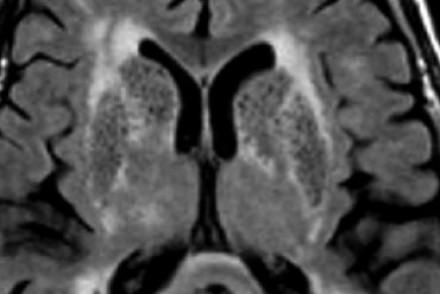

圖片四:FLAIR成像

血管周圍間隙是穿透軟腦膜血管周圍的腦脊液間隙。通常位于基底神經(jīng)節(jié)、腦室周圍、前連合附近以及腦干中間。在MR成像圖像上,在所有序列上的密度與腦脊液的密度相近。與其他白質(zhì)損傷病灶不同,血管周圍間隙在FLAIR和PD成像上呈黑暗模糊影,通常比較小,位于前連合附近的除外,此處的血管周圍間隙比較大。

在上圖中,我們可以看到比較寬的血管周圍間隙和在白質(zhì)中有融合的高密度信號病灶。該圖像很好的顯示了血管周圍間隙和白質(zhì)損傷病灶之間的差異。

由于周圍結(jié)構(gòu)組織的萎縮,血管周圍間隙會隨著衰老和高血壓而逐漸增寬。